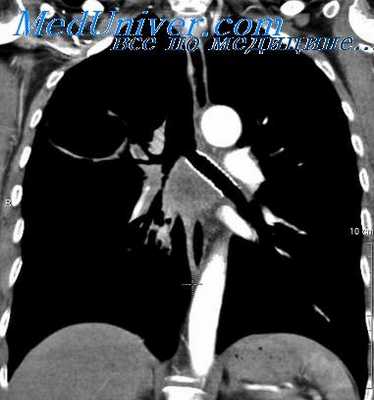

Больной Е., 25 лет, ранен в грудь осколком мины 25/11 2012 г. Поступил в госпиталь через 20 часов в тяжелом состоянии, с выраженным цианозом, одышкой. Пульс 110 ударов в минуту, ритмичный, артериальное давление 120/70 мм ртутного столба, температура 38°. В области рукоятки грудины рана длиной 0,7 см, закрытая сгустком крови. Отека окружающих тканей не отмечается. На рентгенограмме осколок 0,5 см длины располагается в переднем средостении кпереди от дуги аорты. Вокруг него отмечается диффузное затемнение, распространяющееся на корень левого легкого. Выражен симптом Хорнера.

Больной находился в госпитале в течение 5 дней. Постепенно температура снизилась до нормы, исчезла тахикардия и одышка, но симптом Хорнера остался. Больной эвакуирован в хорошем состоянии.

В данном случае имело место слепое ранение средостения, без повреждения крупных сосудов и органов. Течение этого вида травмы было благоприятным, инородное тело в дальнейшем может быть удалено, если появятся жалобы на боли, сердечные нарушения, повышения температуры, зависящие от коррозии металла и инфицирования зоны ранения.